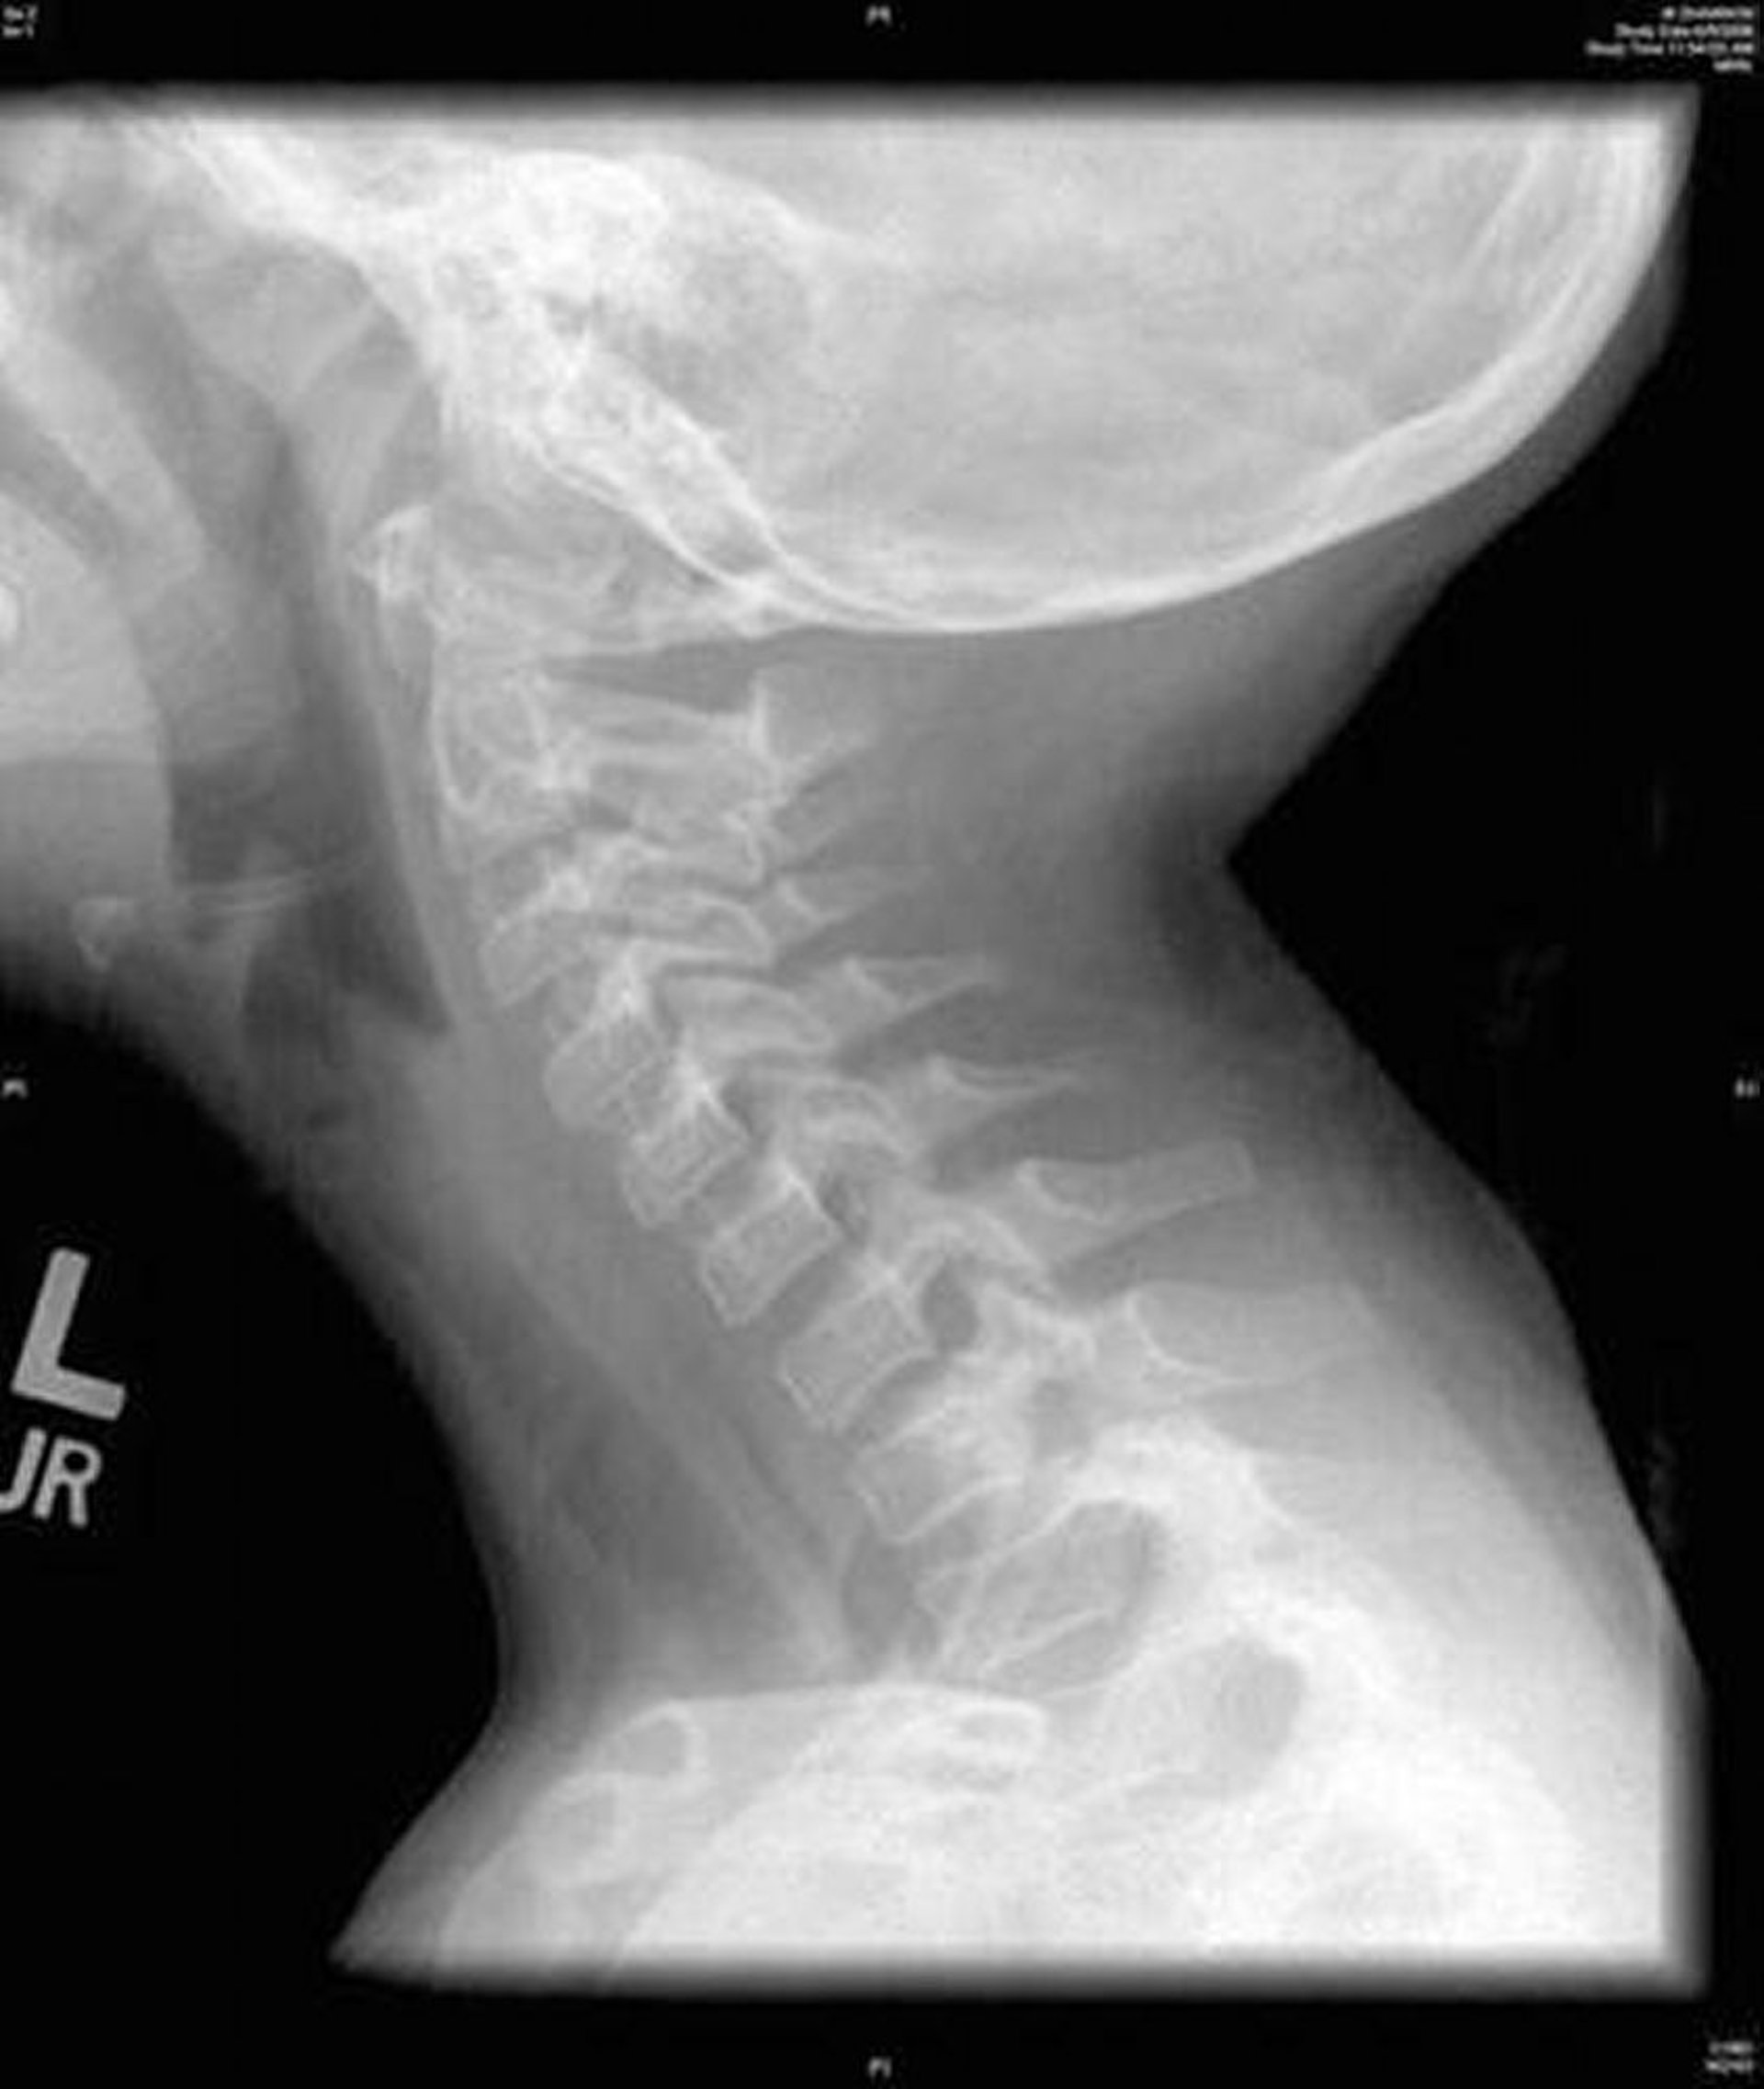

This image shows a lateral radiograph of the neck that shows diffuse irregularity of the trachea characteristic of bacterial tracheitis.